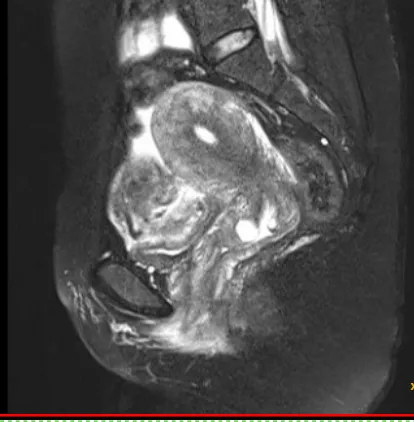

▲ 磁共振图像

近日,妇科接诊了一位46岁的女患者,因下腹剧烈疼痛半天入院,无畏寒、发热,无异常阴道流血,无腹泻。妇检子宫压痛明显。查妊娠试验及C反应蛋白均正常。B超及磁共振提示子宫肌瘤大小约6x5cm。考虑腹痛原因为子宫肌瘤蒂扭转可能性大,予紧急行腹腔镜探查术。术中见肿大坏死的带蒂浆膜下子宫肌瘤6x5cm,予行肌瘤切除,病理学回报子宫平滑肌瘤(大面积梗死,符合扭转的临床诊断)。